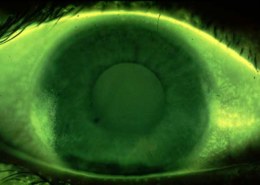

3&9’0 clock staining is the symptoms of what condition when patient is the existing user of RGP lenses

A common complication with corneal GP lenses is 3 and 9 o’clock staining, which is a result of epithelial punctate staining of the peripheral cornea near the edge of the GP lens. These so-called 3 and 9 o’clock areas may not be adequately resurfaced with tears after a blink, thus resulting in small desiccated regions.